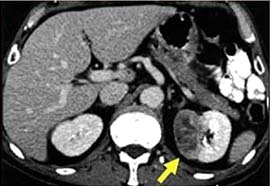

Böbrek yetmezliğine kanamalara böbrek taşına böbrek iltihabına ve yüksek tansiyona sebep olur. Bu kisttin var olduğu hastalarda böbrek rahatsızlığından kaynaklı olarak yüksek tansiyon sorunu ortaya çıkar. Bazı durumlarda ultrason yeterli kalmaz daha şüpheli durumlarda tomografi yada mr yöntemlerine başvurulur. Böbreklerde kitle oluşumu genel olarak doğuştan meydana gelmektedir.